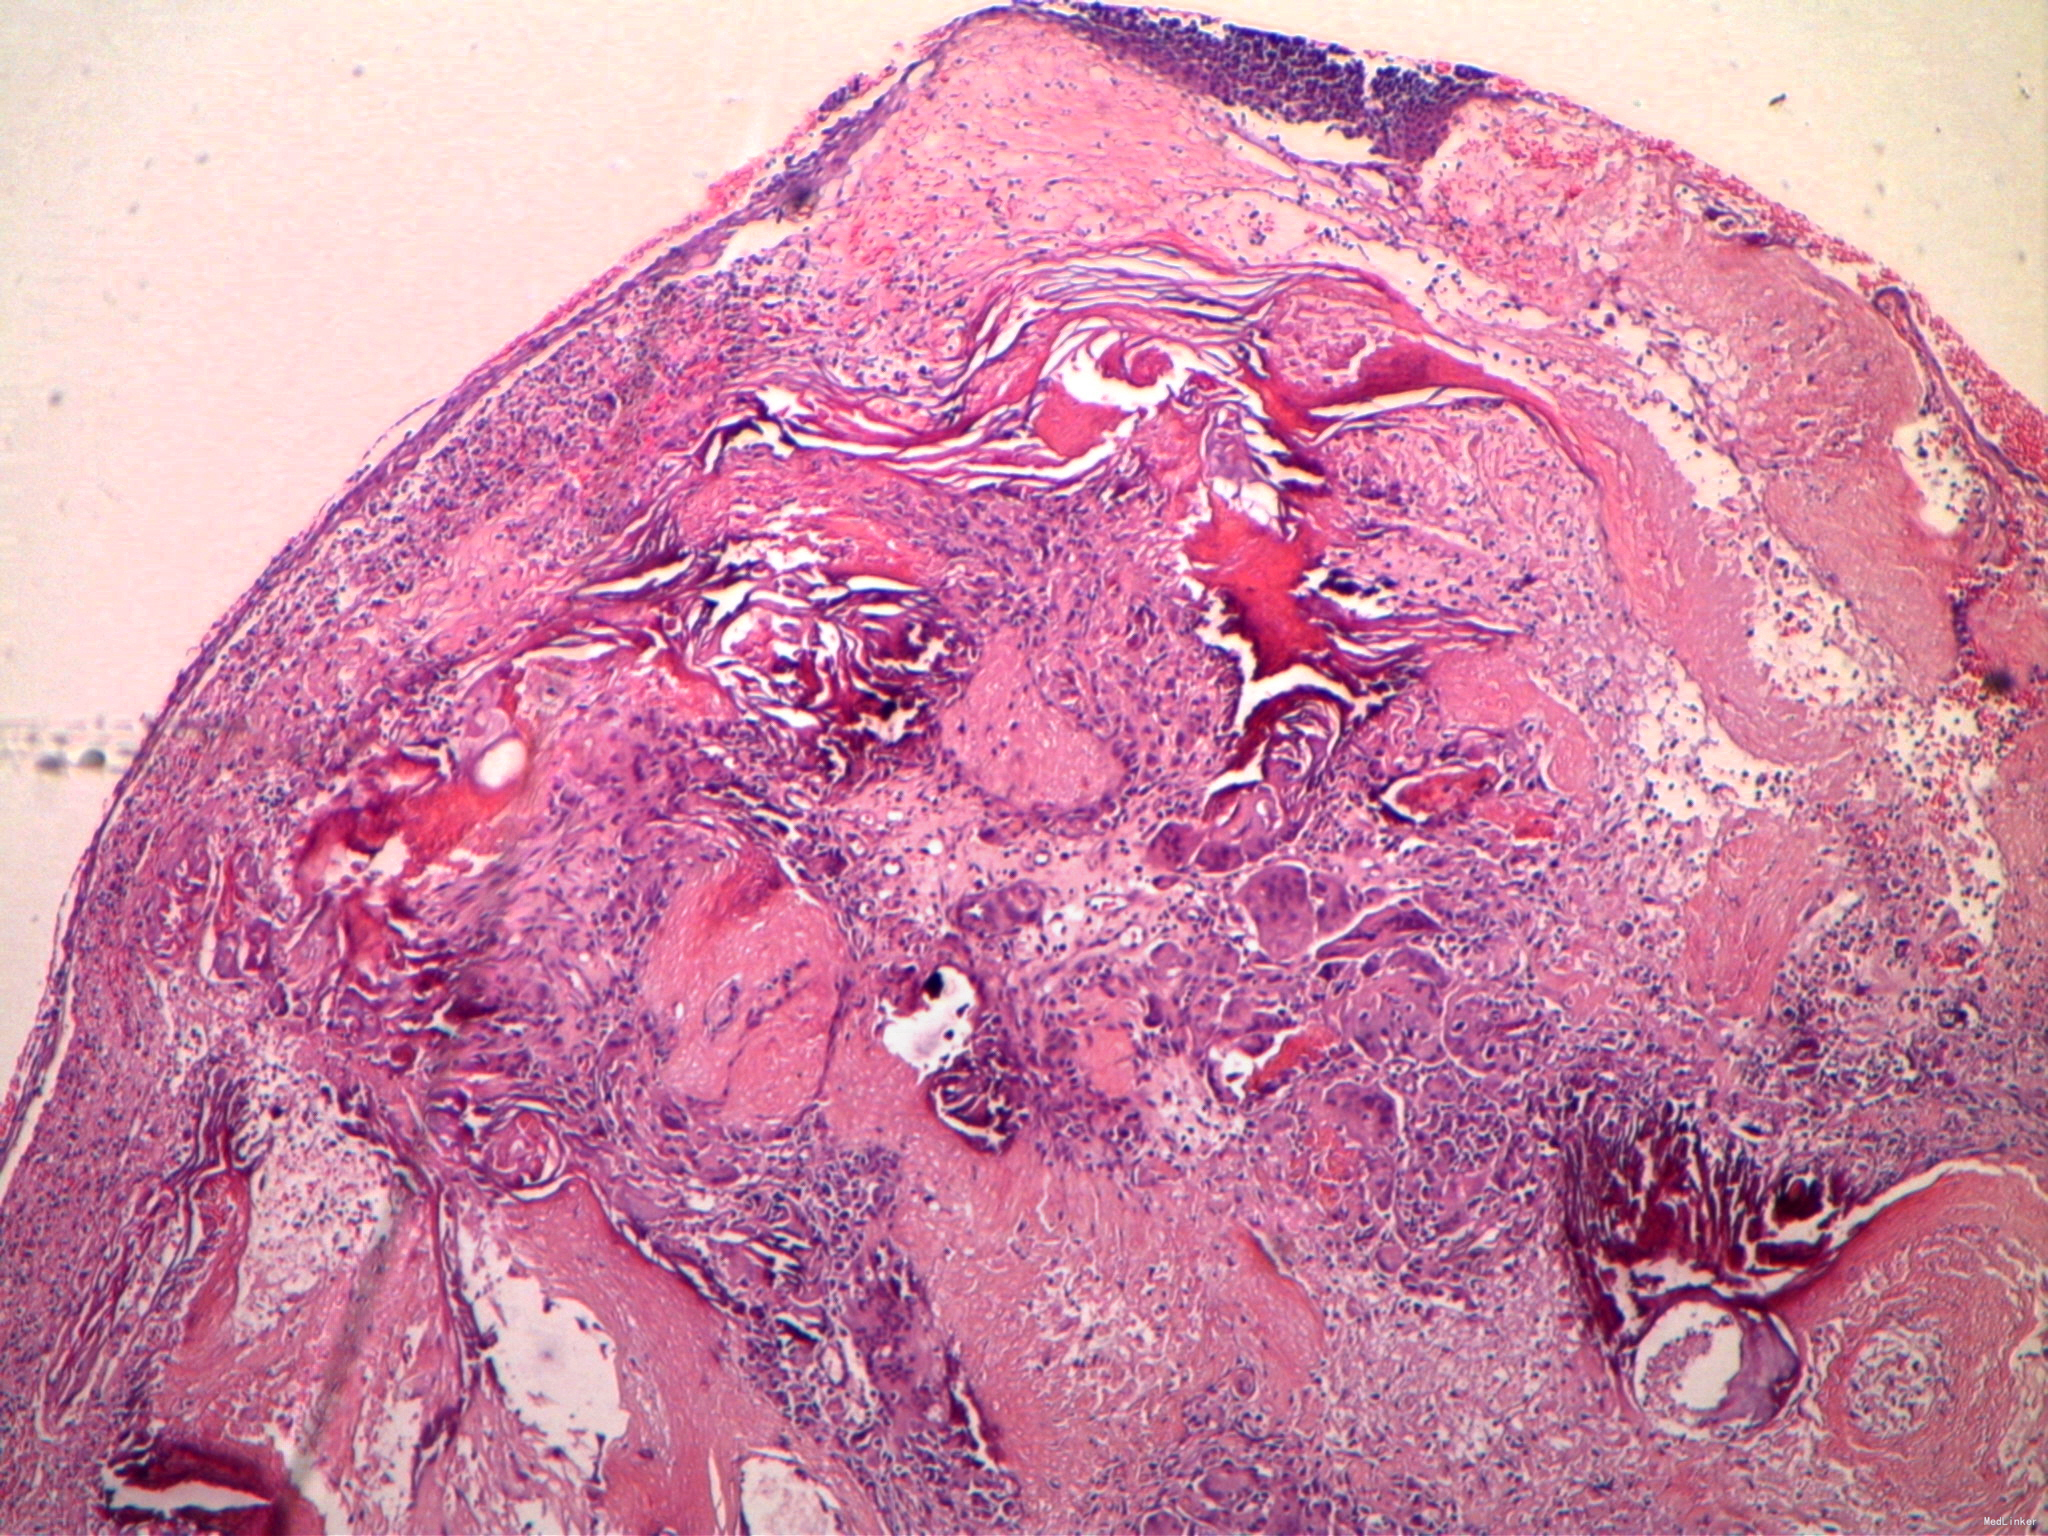

病理检查示:皮下囊肿.囊壁内见嗜碱细胞、影子细胞及钙化区

诊断:钙化上皮瘤。